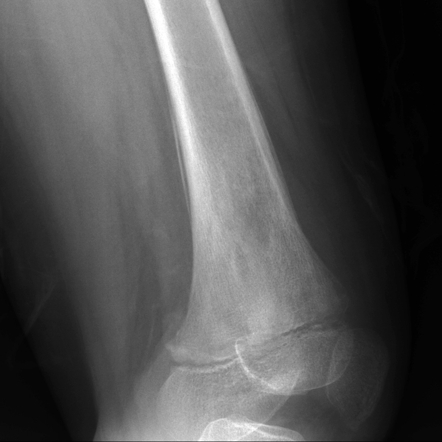

Eosinophilic Granuloma Of Bone: Two ... - Brain And Development

Eosinophilic granuloma of bone: Two case reports (CT) revealed an osteolytic lesion on the left parietal bone. On magnetic resonance imaging (MRI), the lesion corresponded to known as histiocytosis X, and includes the clinical ... Access Full Source